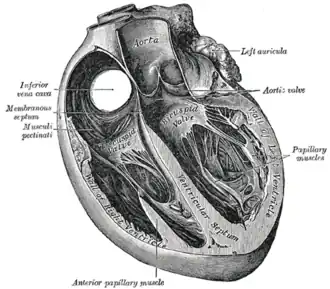

A ventricle is one of two large chambers located toward the bottom of the heart that collect and expel blood towards the peripheral beds within the body and lungs. The blood pumped by a ventricle is supplied by an atrium, an adjacent chamber in the upper heart that is smaller than a ventricle. Interventricular means between the ventricles (for example the interventricular septum), while intraventricular means within one ventricle (for example an intraventricular block).

In a four-chambered heart, such as that in humans, there are two ventricles that operate in a double circulatory system: the right ventricle pumps blood into the pulmonary circulation to the lungs, and the left ventricle pumps blood into the systemic circulation through the aorta.

Structure

Ventricles have thicker walls than atria and generate higher blood pressures. The physiological load on the ventricles requiring pumping of blood throughout the body and lungs is much greater than the pressure generated by the atria to fill the ventricles. Further, the left ventricle has thicker walls than the right because it needs to pump blood to most of the body while the right ventricle fills only the lungs.[1][2]

On the inner walls of the ventricles are irregular muscular columns called trabeculae carneae which cover all of the inner ventricular surfaces except that of the conus arteriosus, in the right ventricle. There are three types of these muscles. The third type, the papillary muscles, give origin at their apices to the chordae tendinae which attach to the cusps of the tricuspid valve and to the mitral valve.

The right ventricle is equal in size to the left ventricle and contains roughly 85 millilitres (3 imp fl oz; 3 US fl oz) in the adult. Its upper front surface is circled and convex, and forms much of the sternocostal surface of the heart. Its under surface is flattened, forming part of the diaphragmatic surface of the heart that rests upon the diaphragm.

Its posterior wall is formed by the ventricular septum, which bulges into the right ventricle, so that a transverse section of the cavity presents a semilunar outline. Its upper and left angle forms a conical pouch, the conus arteriosus, from which the pulmonary artery arises. A tendinous band, called the tendon of the conus arteriosus, extends upward from the right atrioventricular fibrous ring and connects the posterior surface of the conus arteriosus to the aorta.

Shape

The left ventricle is longer and more conical in shape than the right, and on transverse section its concavity presents an oval or nearly circular outline. It forms a small part of the sternocostal surface and a considerable part of the diaphragmatic surface of the heart; it also forms the apex of the heart. The left ventricle is thicker and more muscular than the right ventricle because it pumps blood at a higher pressure.

The right ventricle is triangular in shape and extends from the tricuspid valve in the right atrium to near the apex of the heart. Its wall is thickest at the apex and thins towards its base at the atrium. When viewed via cross section however, the right ventricle seems to be crescent shaped.[4][5] The right ventricle is made of two components: the sinus and the conus. The Sinus is the inflow which flows away from the tricuspid valve. [6] Three bands made from muscle, separate the right ventricle: the parietal, the septal, and the moderator band. [6] The moderator band connects from the base of the anterior papillary muscle to the ventricular septum.[5][7]